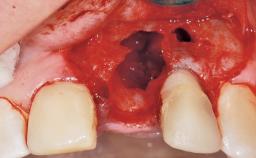

Immediate Placement of an Implant in a Maxillary Left Central Incisor Site

A 33-year-old female patient presented with an upper left central incisor that required extraction after a failed endodontic therapy. The tooth had been traumatized when the patient was a teenager and had undergone several endodontic treatments, including two apicectomy procedures. The patient was in good health and did not smoke. Clinical examination showed that the patient had a high lip line. In full smile, the gingival margins of the upper teeth were visible to the first molars. The gingival margins of central incisors 11 and 21 were only just showing. Examination of tooth 21 confirmed that the tooth was mobile and had hypererupted by 1 mm.

Socket Integrity | Damage to one or more bone walls |

Bone Volume | Damage to one or more socket walls |